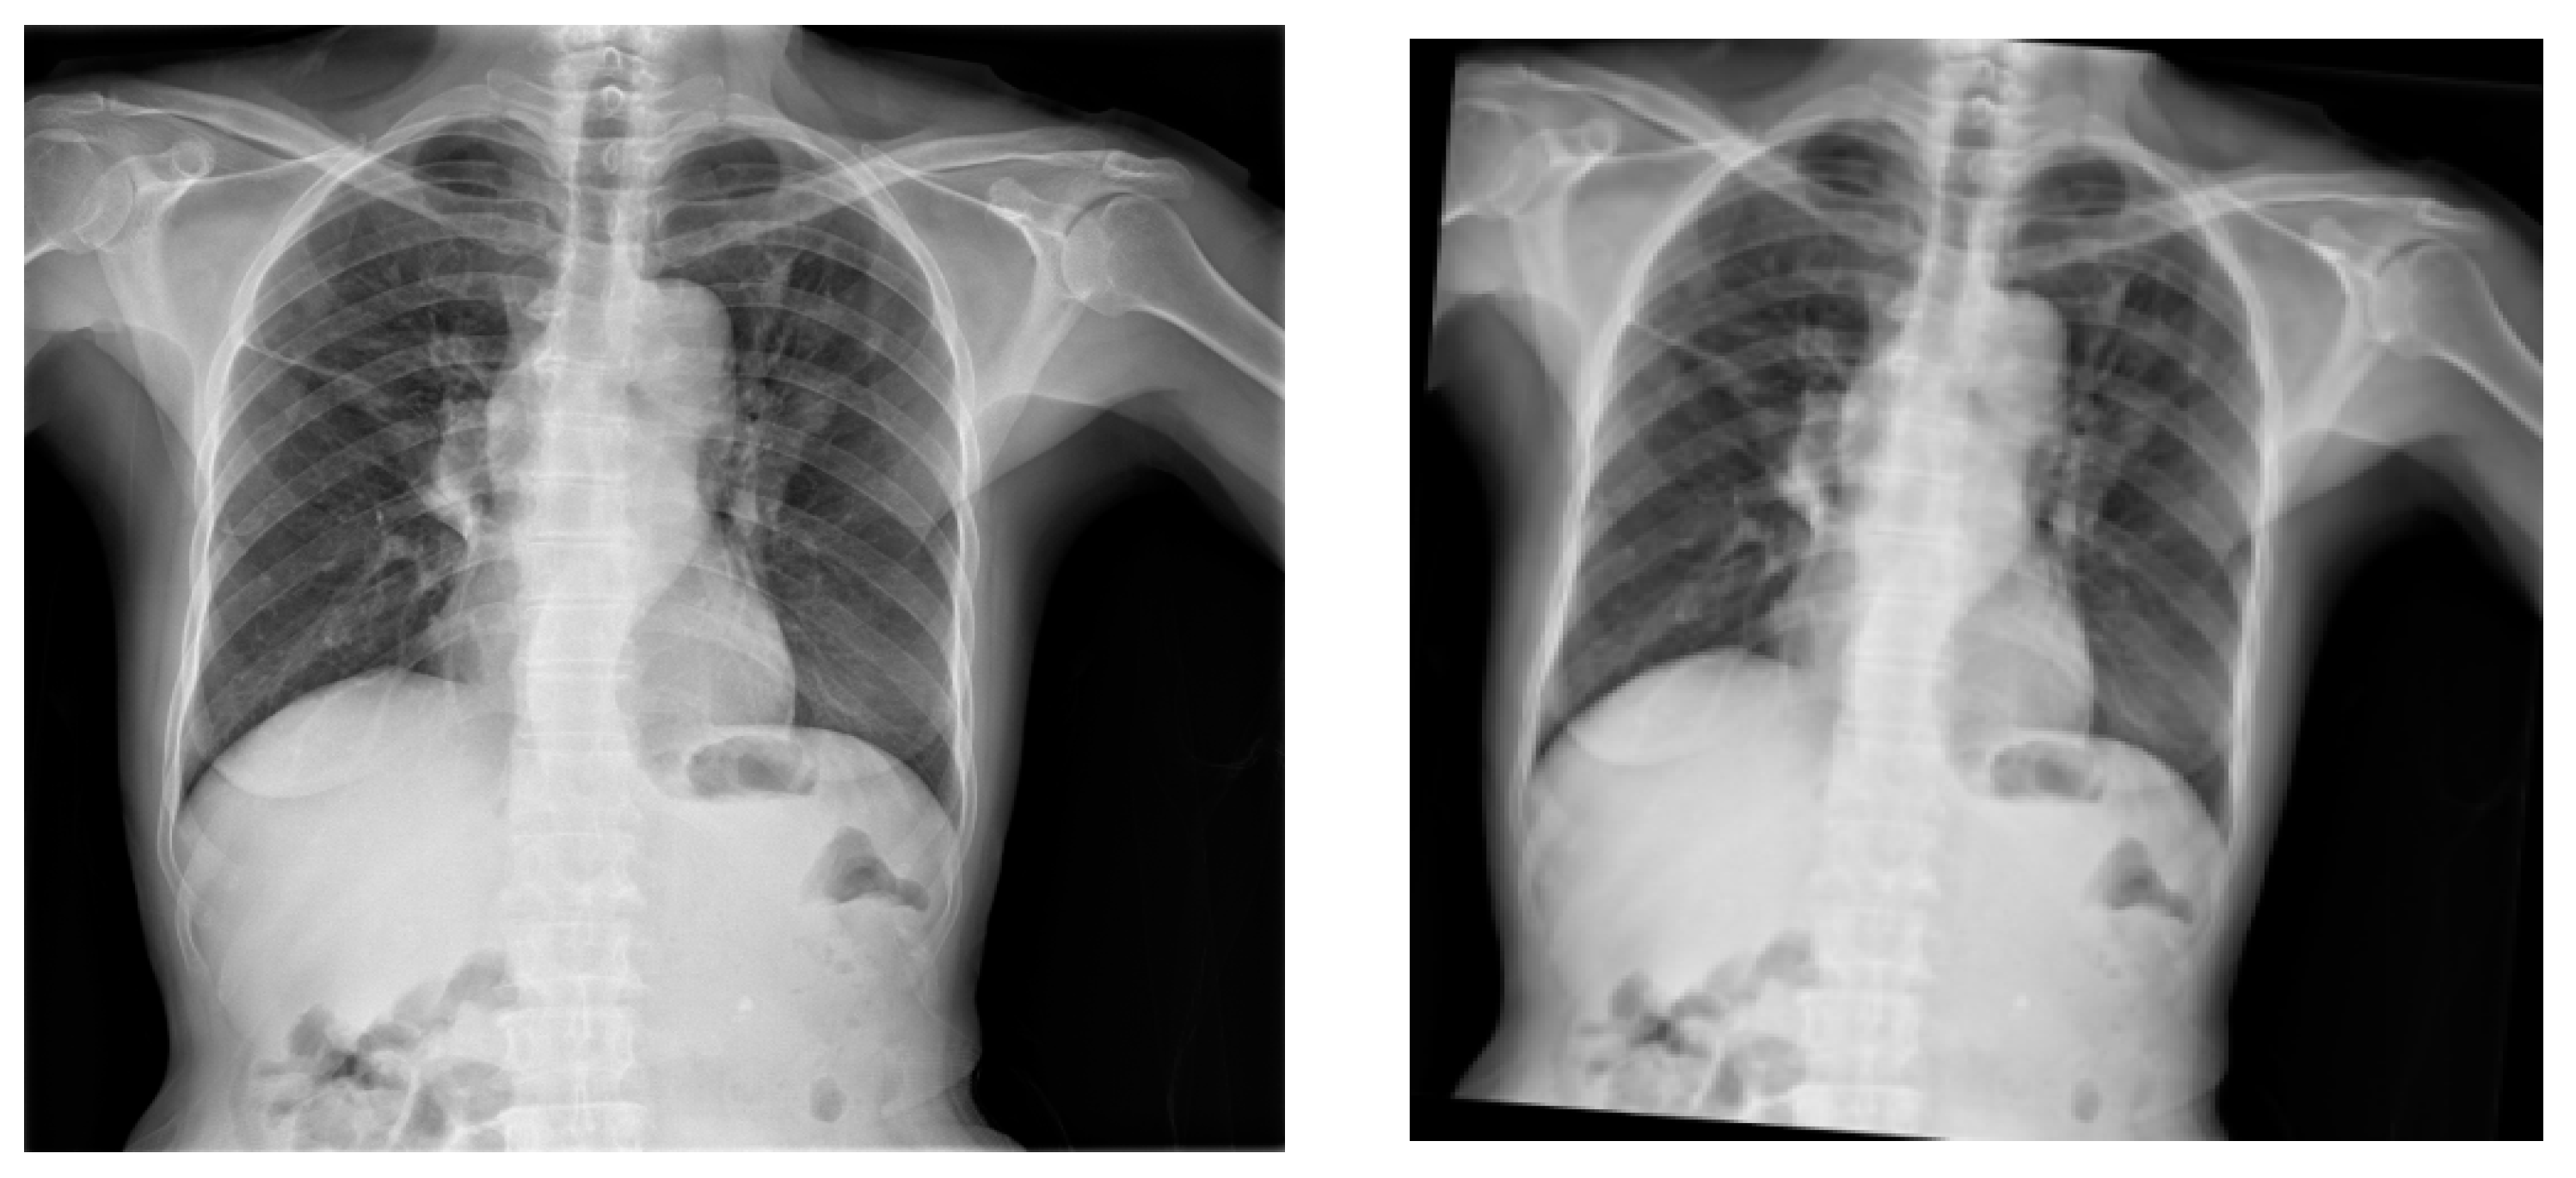

When it comes to X-ray images, rotation is a commonly used augmentation technique, as shown in Figure 5 and Figure 6. To apply a clockwise and anticlockwise rotation transformation to the X-ray image by 5 degrees, the Image library was used. The rotation also had to persist in the respective bounding box, which was also performed with the Image library.

Figure 5. Original X-ray (left image) and the output of the application of anticlockwise rotation of the X-ray images by 5 degrees (right image).

Information 14 00655 g005

Figure 6. Original X-ray (left image) and the output of the application of clockwise rotation of the X-ray images by 5 degrees (right image).

Information 14 00655 g006